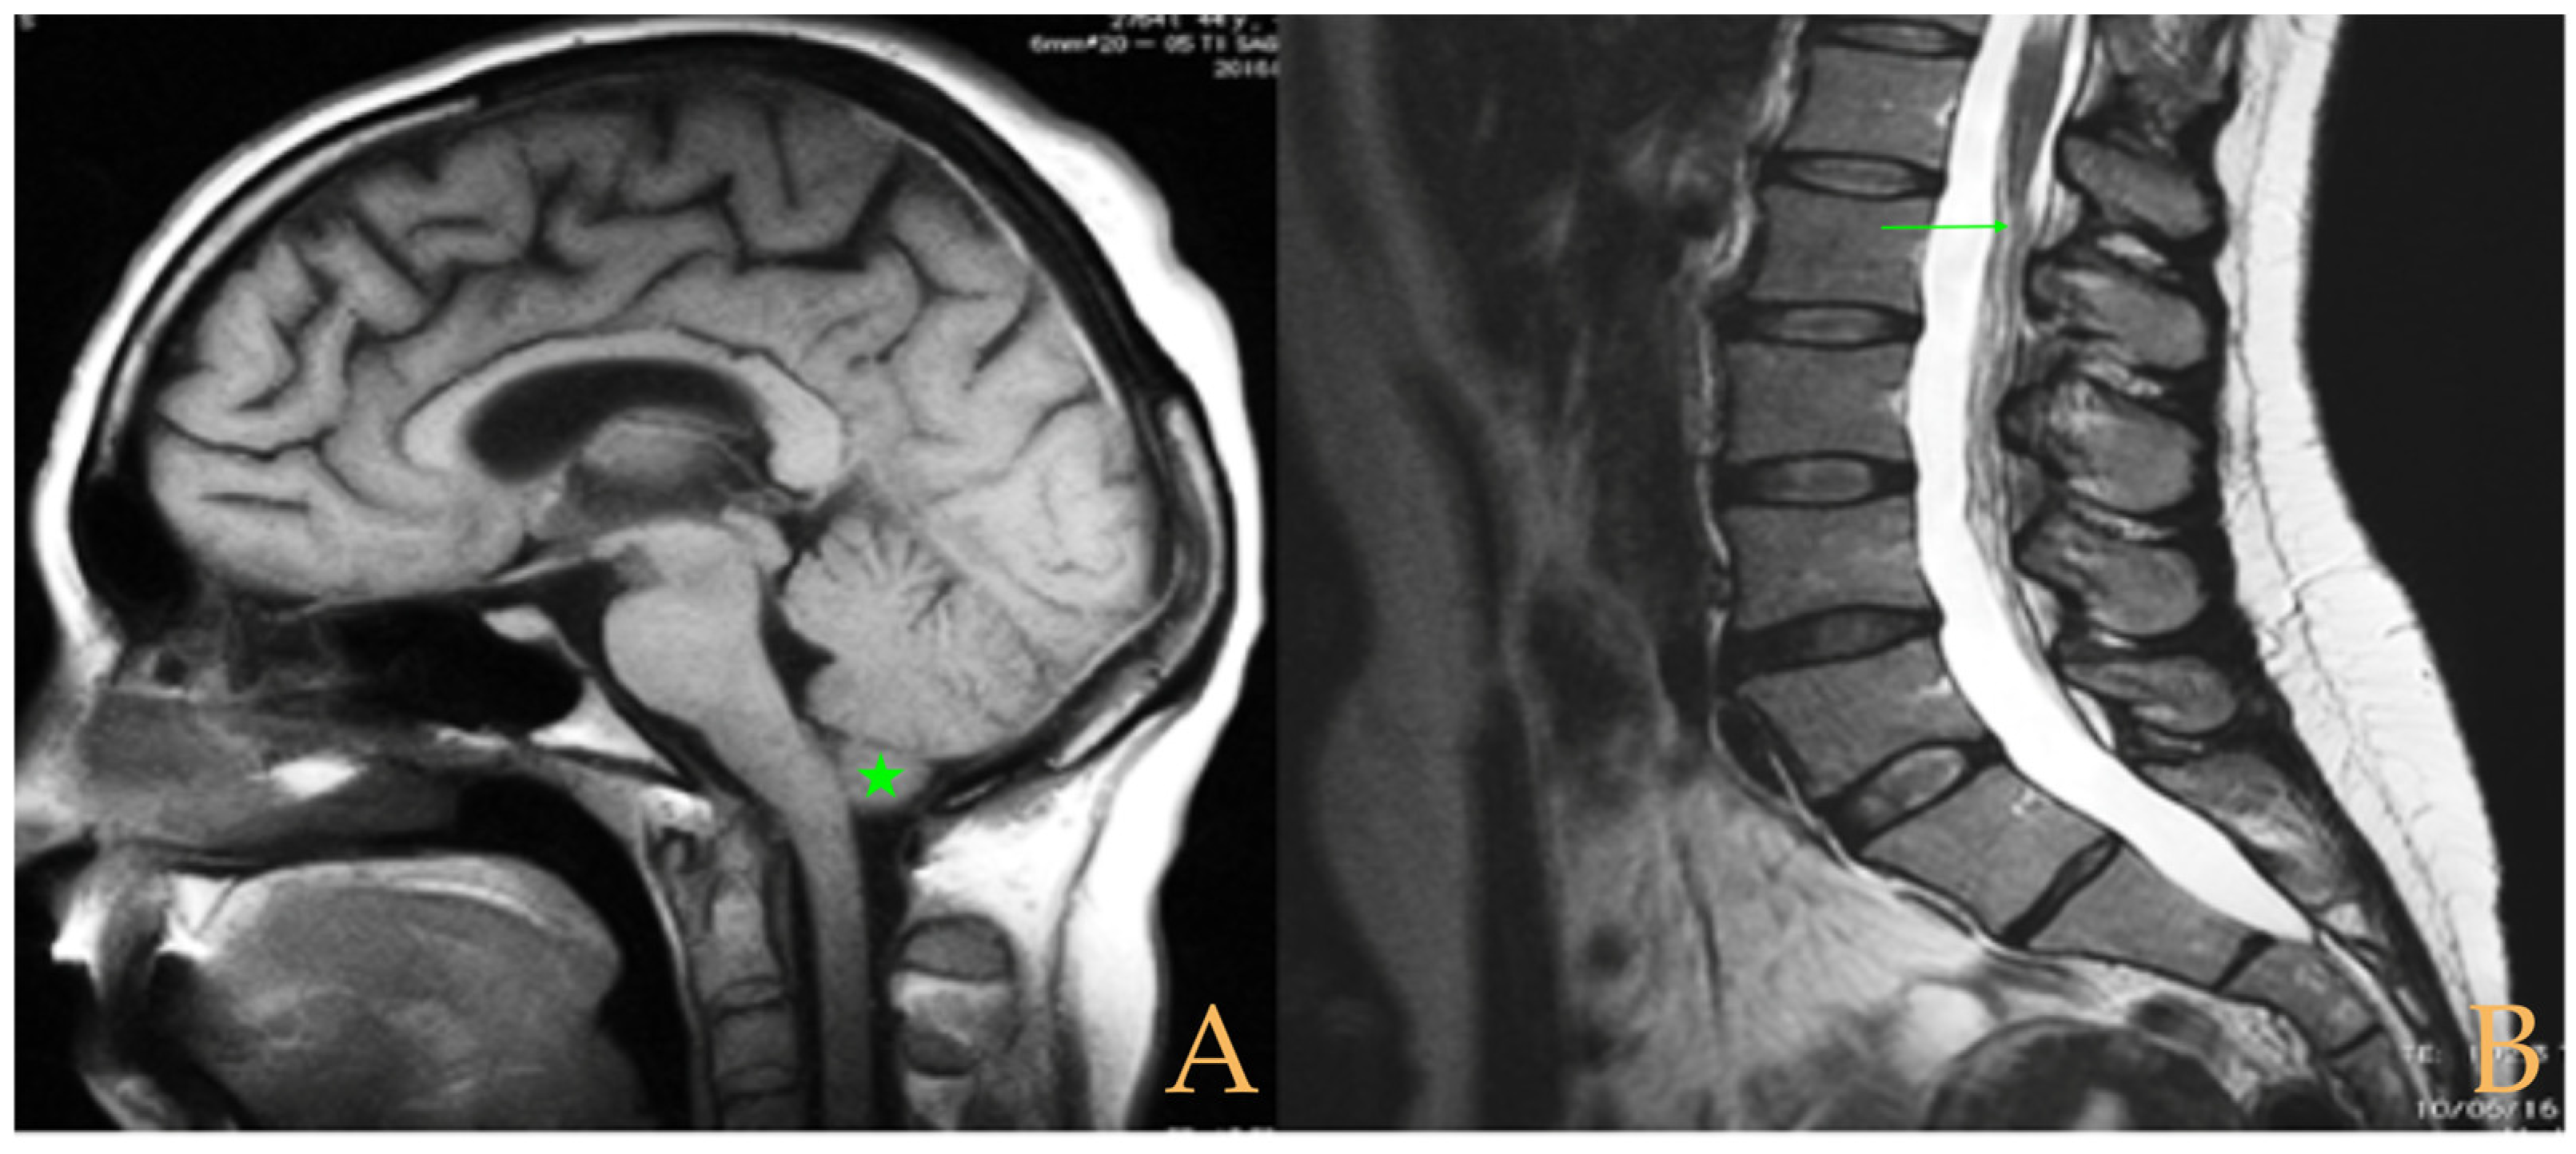

The cranio-vertebral magnetic resonance showed empty sella turcica, discrete descent of the cerebellar tonsils, C4-C5-C6 disc protrusions and cervical hypermobility with a tense medullary aspect in flexion in the incorporated dynamic test, and conus medullaris at the height of the TH12-L1 disc (Figure 3). No scoliosis was observed in the full-spine X-rays. The patient was not operated on. Cases 8 and 9 were very similar and involved previously diagnosed cranio-cervical and atlantoaxial instability. The patient used a cervical collar, as she was afraid that she might suffer spontaneous cervical luxation.

Figure 3. Imaging of patient 3. A: Empty sella turcica (arrow); B: discrete descent of the cerebellar tonsils (arrow); C: C4C5 and C5C6 disc protrusions (arrows); and D: tense spinal cord in cervical flexion (interrupted line).